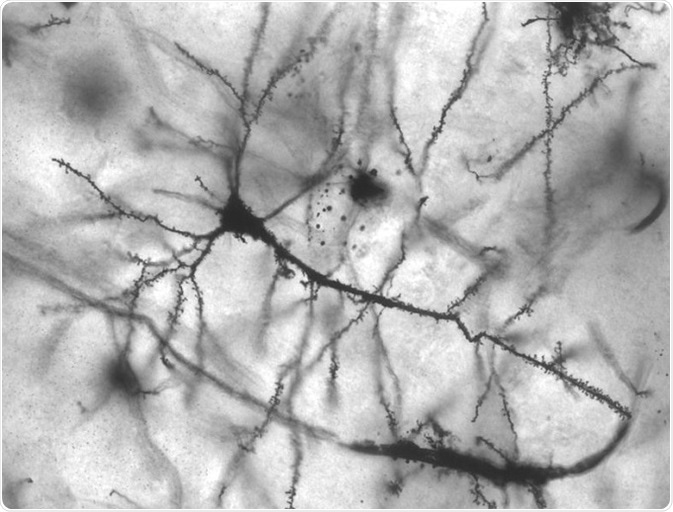

Image: Golgi stained pyramidal neuron in the hippocampus of an epileptic patient. 40 times magnification. Credit: Methoxyroxy~commonswiki/ commons.wikimedia.org.

Neurons have a cell body (soma) and two types of extensions, or processes. One is called a dendrite, and the other one is an axon. Neurons usually have more than one dendrite and one axon. Dendrites receive signals which they then send towards the cell body. The axon also transmit signals, but over longer distances.

Neurons form synapses with each other, which can be seen under a microscope. These are junctions where signals are passed from the axon of one neuron, to a dendrite or cell body of another neuron.